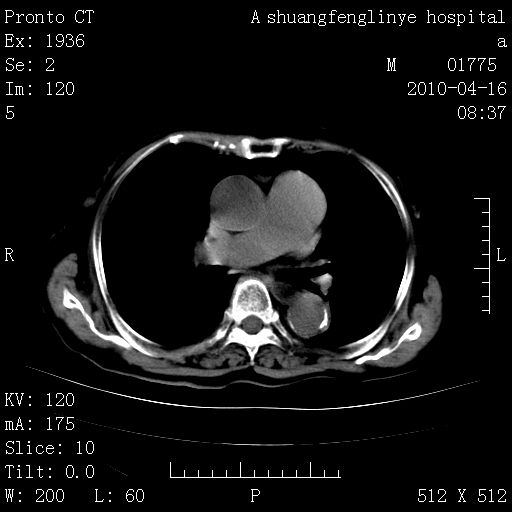

标题: CT25784:咳痰、请会诊!结核? [打印本页]

标题: CT25784:咳痰、请会诊!结核?

陈旧性结核,胃腔扩大,脾脏受压后移

慢支肺气肿,左上陈旧性结核,主动脉冠脉钙化

典型 夹层动脉瘤。 内膜瓣钙化移位

1)左肺上叶结核(纤维、增殖病灶)。2)冠状动脉及主动脉钙化。

1)左肺上叶结核(纤维、增殖病灶)。2)冠状动脉及主动脉钙化。肺动脉高压